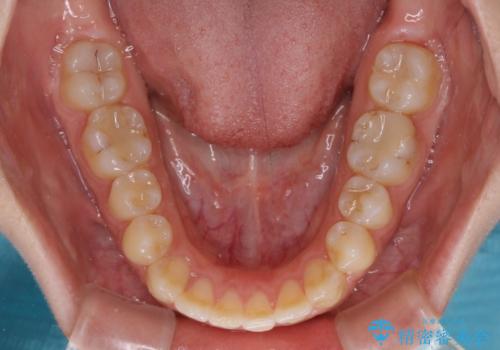

【モニター】オープンバイトをインビザラインで矯正治療

- 前歯の上下スペースによる食べにくさを気にして来院された患者様です。

インビザラインにより上下の前歯の隙間を閉じていくこととしました。

前歯のデコボコの解消と並行して上下の奥歯を圧下させるようにすることで、前歯を接触させるように計画しました。

上下の隙間に舌が入り込むことがオープンバイトの原因であったため、舌の筋肉のトレーニングも並行して行い、後戻りの抑制を図りました。